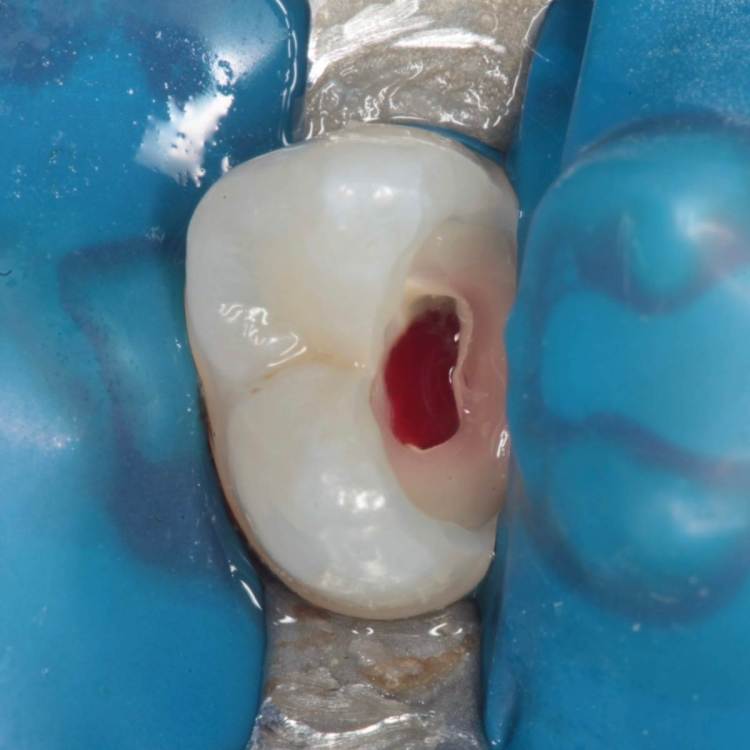

Доступ проводился шаровидным бором, синим финиром и аналогом бора endo z.

Эндо 25.06, 40.04, 60.02. Обтурация инжекторной техникой. Восстановление гармонайз а3 и желтая текучка от эстелайта (говорят ее сняли с производства, жаль, очень классный материал был)